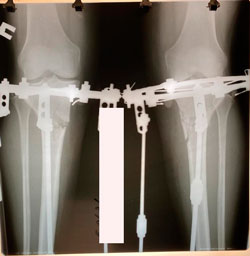

Исходник - 50 лет.

Дата операции - 15.12.2020

на фиксации

рентген перед фиксацией